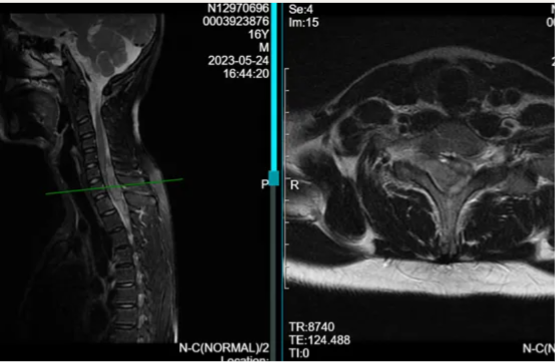

脊髓海绵状血管瘤并不是真正意义上的肿瘤,而是一种脊髓血管畸形,是隐匿性血管畸形中最为常见的一种